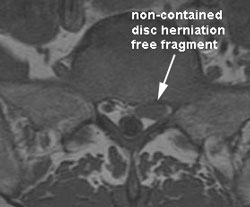

About A Juneau Non-Contained Disc Herniation

Non-contained discs (aka free fragment or extrusion) may be managed well conservatively. Non-contained lumbar disc herniations show better non-surgical relief than contained discs. (1) MRI helps in visualizing and monitoring the disc and nerve root changes while care is administered. (2) Nine of 11 non-contained discs shrunk 50% to 100% non-operatively. (3) Larger non-contained discs reduce the most. (4) Research notes spontaneous resorption of intradural disc material via macrophage and angiogenesis (the process of new blood vessels forming) within the disc. (5) As a matter of fact, free fragments (non-contained discs) absorb and decrease in size more than protruding (contained) discs. When the non-contained fragment moves, an even greater reduction in size is seen. (6) Phagocytes and cytokines play a role in helping resorb the non-contained disc. (7, 2)